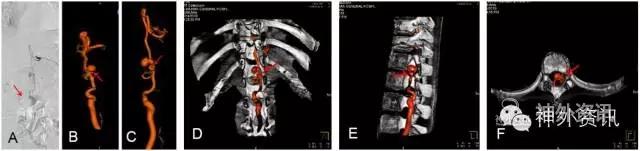

脊髓血管造影,尤其是经皮穿刺股动脉选择性脊髓血管造影,是诊断脊髓血管疾病的金标准。至今,由于影像技术、DSA血管造影机诸多后处理功能的进步,如三维成像技术(three-dimensional imaging technology;图1)、最大密度投影成像(maximum intensity projection,MIP;图2)、双容积重建(double volume,DV;图3)与三维影像融合技术(three dimensional image fusion technology;图4)及我们研究开发的三种技术的动态成像技术(dynamic image fusion technology),可以给出冠状位从前到后再从后到前、矢状位从左到右再从右到左、轴位从上到下再从下到上的全方位多角度动态立体解剖影像(图5),就更提高了对脊髓血管疾病诊断的认识和治疗水平。因此,应该说这些三维融合影像才是脊髓血管疾病诊断的金标准[1,2]。

图3: 胸段硬脊膜动静脉瘘(SDAVF),↑示瘘口。A. 2D-DSA;B、C. 3D-DSA;D~F. 双容积重建冠状位、矢状位与轴位融合影像。

图3: G. 动态双容积重建冠状位融合影像。

图3: H. 动态双容积重建矢状位融合影像。

图3: I. 动态双容积重建轴位融合影像。

图3: J、K. 最大密度投影(MIP)冠状位、矢状位融合影像,可了解瘘与脊椎骨的上下左右前后的解剖关系。

图3: L. 动态旋转MIP。